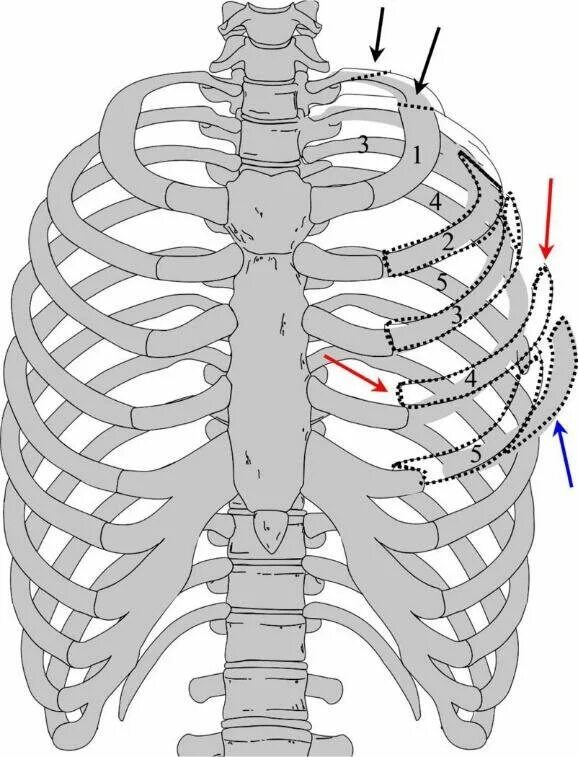

Множественные ребра